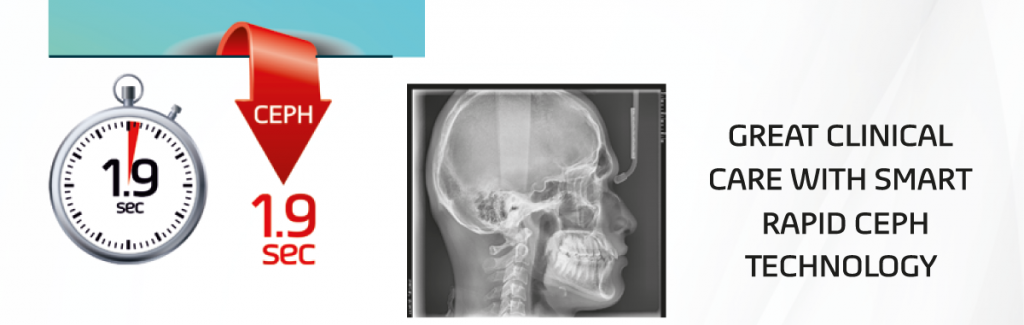

The next step in cephalometric technology vatech’s new Rapid CEPH minimizes motion artifacts & enables faster diagnostic workflow while providing the highest quality digital images.